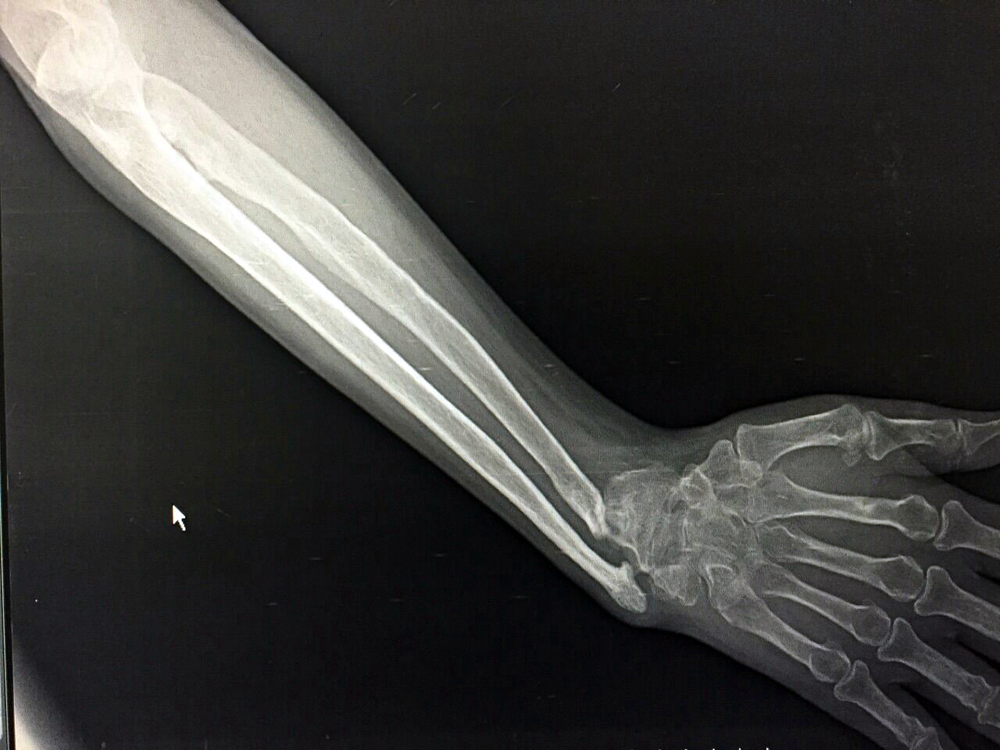

Wrist Deformity Correction